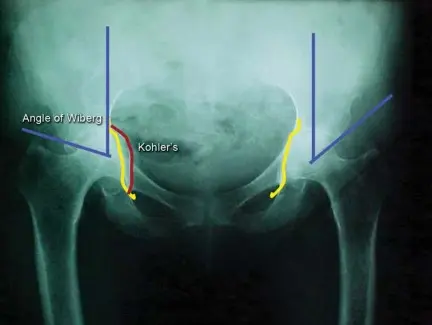

يُعد التصوير الإشعاعي الأمامي الخلفي (AP) للحوض أمراً حاسماً لتشخيص انتبار الحُق وتحديد شدته. يستخدم الأطباء علامات إشعاعية معينة لتقييم الحالة:

خط كوهلر (Kohler’s Line):

وهو خط يمتد على طول الجدار الإنسي للحُق. يعتبر انتبار الحُق موجوداً إذا برز الجدار الإنسي للحُق إنسياً (داخلياً) عن هذا الخط بمسافة 3 مم للرجال أو 6 مم للنساء.

زاوية ويبرغ (Wiberg’s Center-Edge Angle):

تستخدم هذه الزاوية لتقييم خلل التنسج الحُقي. إذا تجاوزت الزاوية 40 درجة، فإنها قد تشير إلى انتبار الحُق.

هذه القياسات تساعد الأستاذ الدكتور محمد هطيف وفريقه في صنعاء على تحديد مدى الانتبار وتخطيط العلاج المناسب بدقة متناهية، مما يضمن أفضل النتائج للمرضى.

*

كما ذكر سابقاً، يُشير البروز الإنسي عن هذا الخط بمسافة معينة إلى وجود الانتبار.

تساعد في تقييم مدى تغطية رأس الفخذ بواسطة الحُق.

شدة الانتبار

يمكن تقييم شدة الانتبار عن طريق قياس هجرة رأس الفخذ بعد خط كوهلر (Ilioischial line). استخدم سوتيلو غارزا وتشارنلي هذا الخط كمرجع لقياس موقع الحُق. تُستخدم هذه المسافة لتحديد الحالة على أنها خفيفة (1 إلى 5 مم)، أو متوسطة (6 إلى 15 مم)، أو شديدة (>15 مم). وبالمثل، يمكن قياس الزيادة في زاوية ويبرغ إشعاعياً.